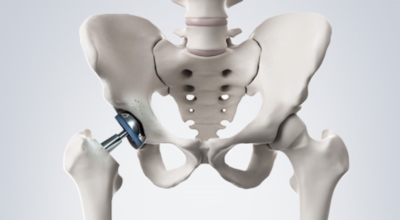

고관절 통증 치료에는 크게 약물 치료와 물리 치료가 있습니다. 고관절염의 진행을 늦추거나 증상을 완화하기 위한 목적으로 항염증제 및 진통제를 투여합니다. 고관절 통증을 조기에 치료하면 약물치료 외에 물리치료로 약 50% 정도 큰 효과를 볼 수 있습니다. 게다가, 보통 고관절 증상 관리에 도움이 되는 요가, 수영, 스트레칭은 고관절 예방과 치료에 도움이 됩니다.